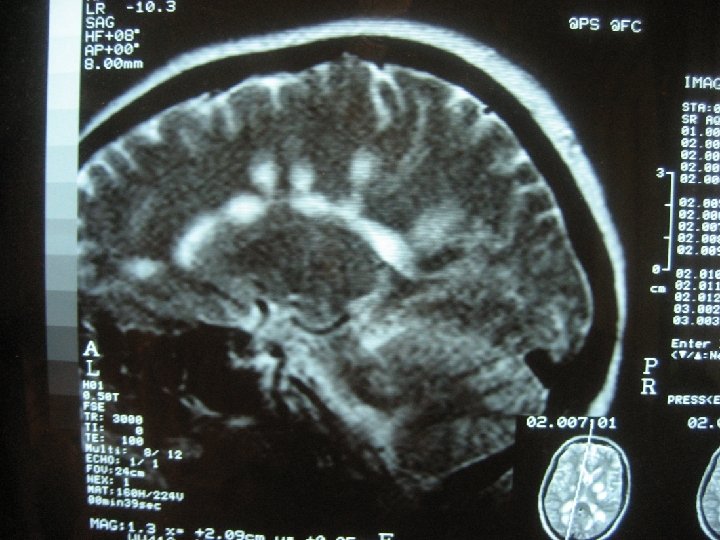

Арахноидит (лептоменингит) - хронический диффузный аутоиммунный пролиферативный спаечный процесс преимущественно паутинной и мягкой оболочек мозга. Истинный (актуальный) арахноидит: активный спаечный процесс аутоиммунной природы, протекающий с образованием антител к оболочкам мозга, продуктивными изменениями в виде гиперплазии арахноэндотелия, приводящий к гибели ячей и облитерации ликвороносных каналов в субарахноидальном пространстве. Характерна диффузность поражения оболочек с вовлечением молекулярного слоя коры, иногда эпендимы желудочков, хореоидного сплетения. Течение хронически прогредиентное и интермиттирующее. Резидуальное состояние после нейроинфекции или черепно-мозговой травмы с исходом в облитерацию, фиброз оболочек (обычно ограниченной распространенности), с образованием сращений и кист на месте некроза. Имеет место полный или частичный регресс симптомов острого периода (исключение - эпилептические припадки). Прогредиентность, как правило, отсутствует.

- конвекситальный арахноидит - эпилептические припадки (у 35% больных). Часты вторично генерализованные парциальные припадки (джексоновские). -базилярный арахноидит (у 27% больных) может быть распространенным или локализоваться преимущественно в передней, средней черепной ямке, в межножковой или оптико-хиазмальной цистерне. В процесс вовлекаются многие черепные нервы на основании мозга (I, III-VI пары), чем и определяется клиника заболевания. Возможна также пирамидная недостаточность. Общемозговые симптомы выражены легко и умеренно. Психические нарушения (утомляемость, снижение памяти, внимания, умственной работоспособности) чаще наблюдаются при арахноидите передней черепной ямки.

оптико-хиазмальный арахноидит. Начальные симптомы появление сетки перед глазами, прогрессирующее снижение остроты зрения, чаще сразу двустороннее, в течение 3 -6 месяцев. На глазном дне - вначале неврит, затем атрофия дисков зрительных нервов. Поле зрения - концентрическое, реже битемпоральное сужение, одноили двусторонние центральные скотомы. - арахноидит задней черепной ямки (у 23% больных), обычно постинфекционный, отогенный. При преимущественной локализации в области мосто-мозжечкового угла раньше проявляется поражение VIII пары черепных нервов (шум в ушах, снижение слуха, головокружение). В дальнейшем страдает лицевой нерв, выявляются мозжечковая недостаточность, пирамидная симптоматика.